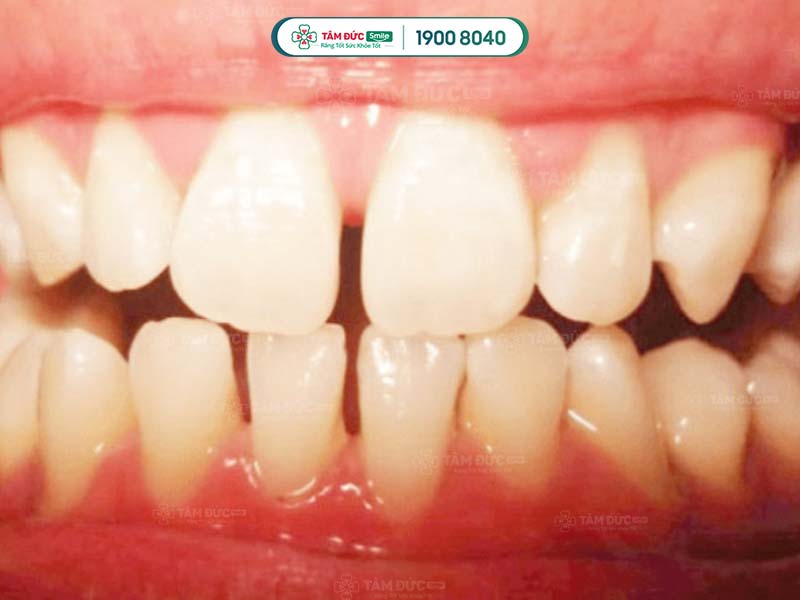

Răng thưa xuất hiện tại bất kỳ vị trí nào ở cả 2 hàm răng: hàm trên và hàm dưới. Tuy nhiên, tỷ lệ răng thưa hàm dưới thường cao hơn hàm trên. Răng bị thưa ở hàm dưới do các răng này phát triển không khít vào nhau, tạo kẽ hở quá lớn giữa các răng tại vị trí hàm dưới.

Mức độ nghiêm trọng tùy thuộc vào vị trí và kích thước của răng thưa. Vấn đề này xuất phát từ nhiều nguyên nhân, không chỉ ảnh hưởng đến tính thẩm mỹ, mà còn gây ra các biến chứng răng miệng khác.

Hình ảnh răng thưa giữa các răng có khoảng hở tạo điều kiện thuận lợi cho thức ăn giắt vào